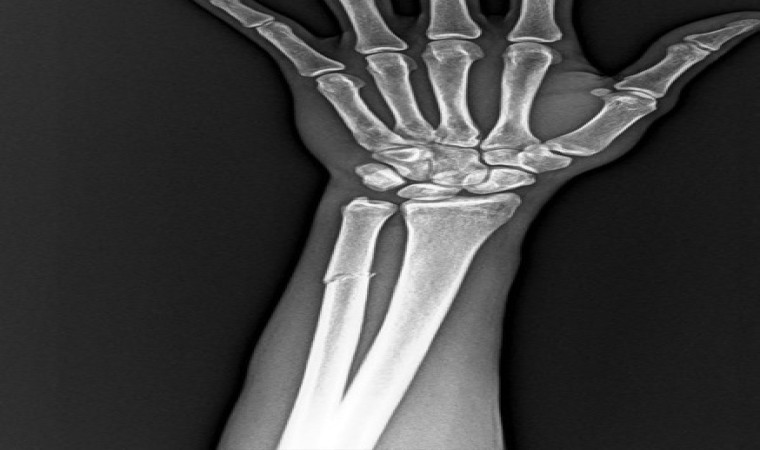

RAMS Başakşehir ile oynanan karşılaşmada mücadele sırasında sakatlanarak oyundan alınan Onuachu’nun sağlık durumu ile ilgili kulübü Trabzonspor bir açıklama yaptı. Yapılan açıklamada, "Futbol A takımımızın Başakşehir ile oynadığı karşılaşma esnasında sakatlanarak oyundan çıkan futbolcumuz Paul Onuachu’nun yapılan muayenesinde sol kasık bölgesinde kas (adduktor kas grubu) yaralanması ve sol ön kolda darbeye bağlı ayrışmamış kemik (ulna) kırığı tespit edilmiştir. Oyuncumuzun tedavisine sağlık ekibimizce başlanmıştır. Oyuncunun sahalardan ne kadar süre uzak kalacağı yapılacak tedavinin ardından belli olacak" ifadelerine yer verildi.